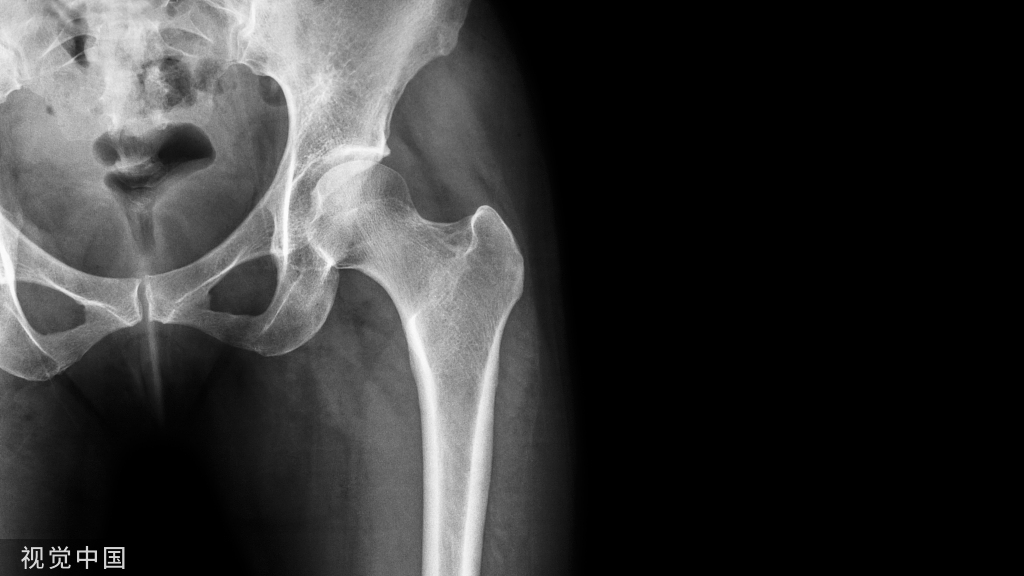

3、X线表现

早期检查正常,逐渐出现关节间隙狭窄、软骨下骨质硬化及囊性变、关节边缘骨赘形成、关节内游离骨片。严重者可以出现关节变形和半脱位。